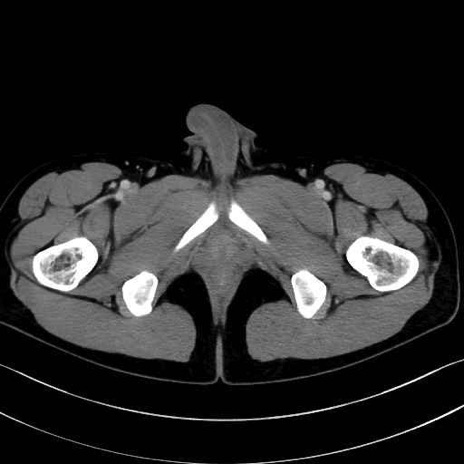

梨状筋(piriformis muscle) のCT画像の解剖

大腿方形筋 (Quadratus femoris)

5. 大腿前面(大腿四頭筋群・伸筋群)

縫工筋 (Sartorius)